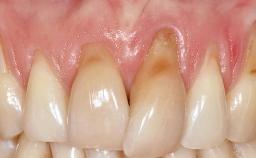

GBR and Soft-Tissue Augmentation Following Explantation to Rehabilitate a Soft- and Hard-Tissue Defect

It is sometimes necessary to remove and replace compromised implants. This case is a clear example of the need for multiple steps to achieve an optimal therapeutic result for patients with non-salvageable implants. It illustrates how the lost soft and hard tissues were rebuilt in a sequence that improved the healing of the hard tissues and assured their long-term stability. The 35-year-old healthy patient presented with clinical attachment loss on the proximal and lingual surfaces of the natural dentition. Some gingival recession was present on natural teeth, particularly in the posterior sextants (S1, S3, S4, and S6).